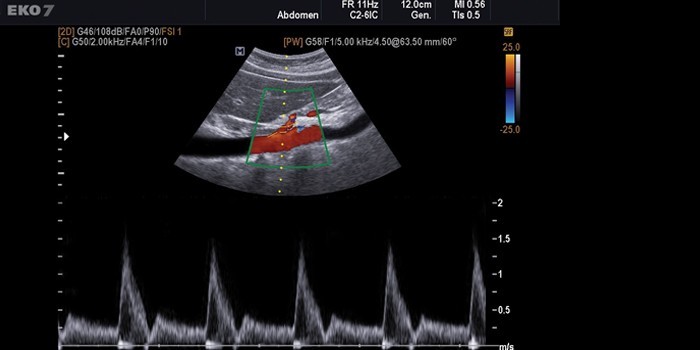

Триплексное сканирование

УЗИ сосудов нижних конечностей этого типа самое быстрое по времени, точное, но цена на него выше, чем на остальные. Оно расширяет возможности дуплексного, добавляя режимы цветного допплера, т.е. цветного изображения движения крови в сосудах, по которому более наглядно можно судить о направлении кровотока и его скорости, а также позволяя более точно оценить проходимость сосудов и степень стеноза. Достигаются три цели, что и определило название метода – триплекс:

- исследуется анатомия сосудов;

- оценивается кровоток;

- производится точная оценка проходимости сосудов в цветовом режиме.